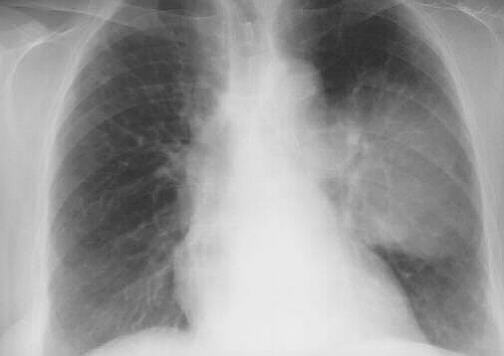

AP viewleft lateral view

Chest X-Ray demonstrating 10.0x6.0 cm mass in Left lower lobe, apical segment.